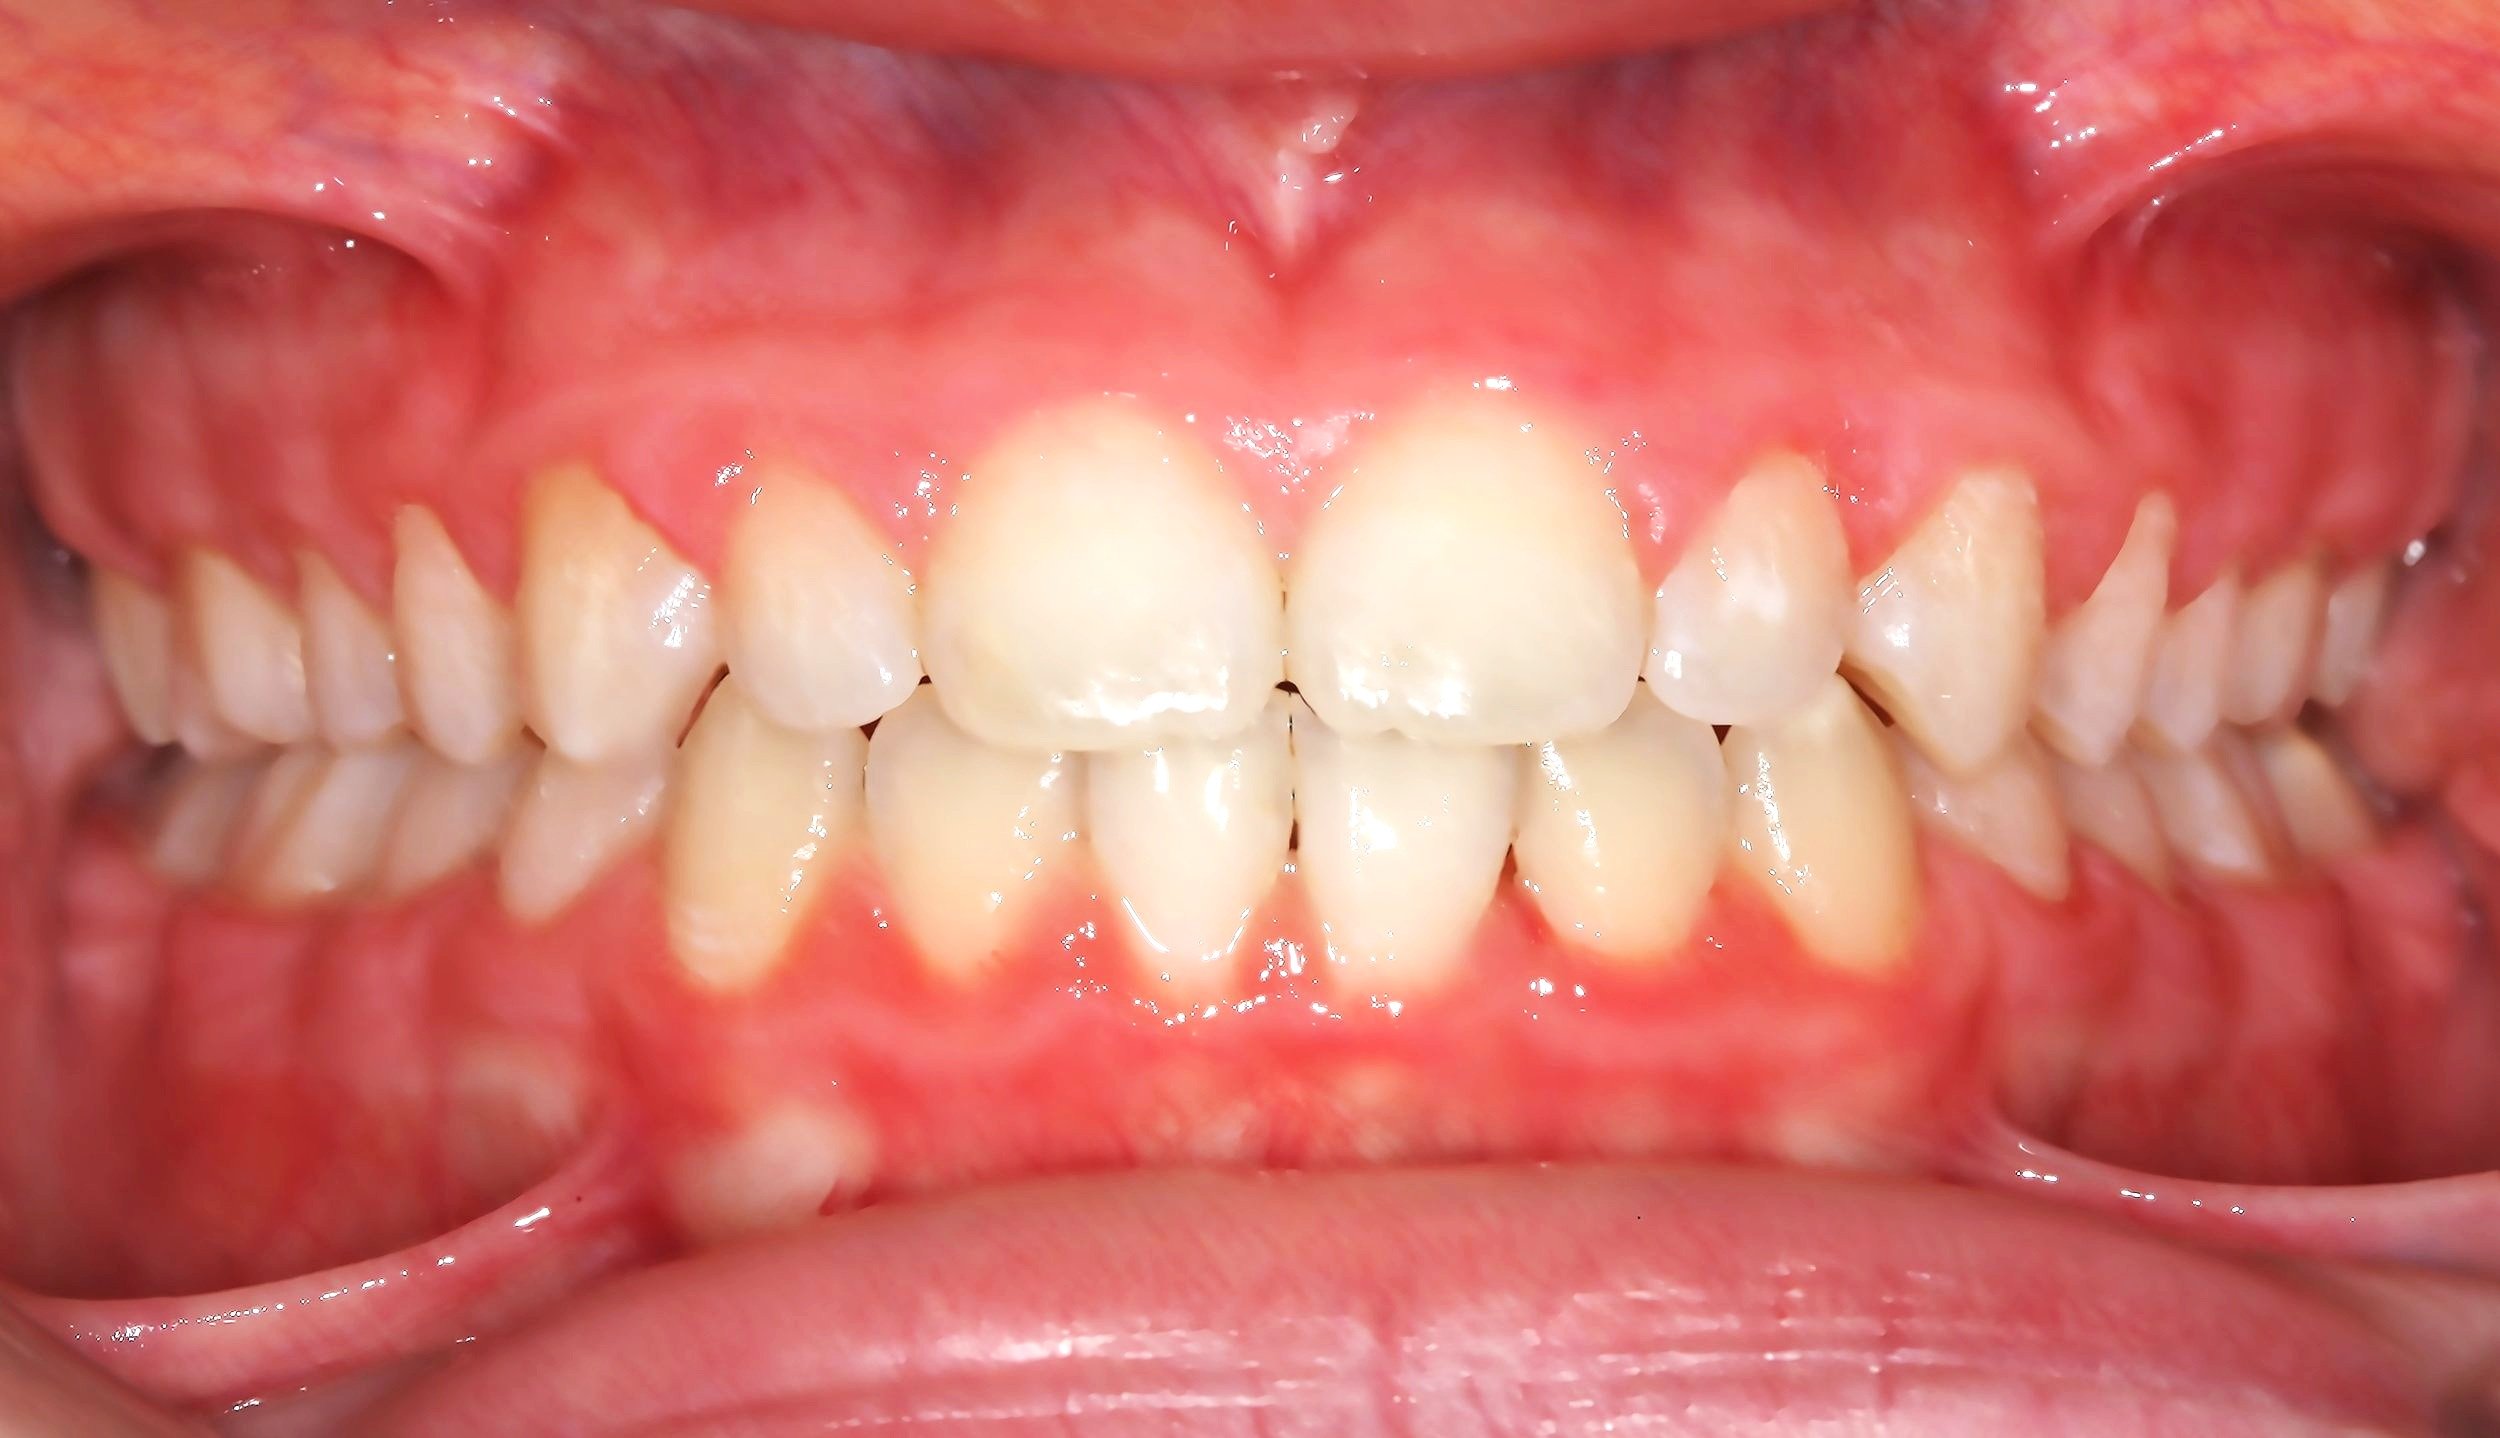

CASO ESTRATTIVO

In alcuni casi, per allineare correttamente i denti senza creare problemi come recessioni gengivali o danni all’osso di supporto, è necessario ricorrere a estrazioni strategiche. Questo accade quando lo spazio in arcata è insufficiente per accogliere tutti i denti in una posizione stabile e armoniosa. Estrarre alcuni elementi dentari permette di ottenere un risultato estetico e funzionale migliore, garantendo una masticazione corretta e preservando la salute dei tessuti gengivali e ossei.

AFTER

Trattamento con 4 estrazioni di una malocclusione di classe II con proclinazione degli incisivi superiori e inferiori.